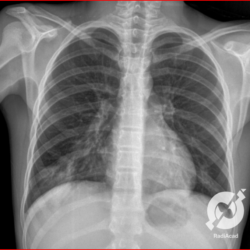

E o nome dado a esta alteração radiográfica que corresponde à substituição do ar alveolar por líquido é a consolidação alveolar.

Uma consolidação alveolar é, por definição, uma opacidade (imagem densa, branquinha) homogênea ou às vezes heterogênea (pela presença de calcificações ou cavidades), de limites mal definidos, exceto quando toca a pleura da parede ou das cissuras pulmonares. É um termo usado tanto em radiografia, como em tomografia computadorizada. Na tomografia, um outro termo é usado: vidro fosco, que é uma opacidade (branquinha mas não tanto como a consolidação), que borra o pulmão mas deixa ver os vasos de permeio (igual bigode de adolescente: dá pra ver todo o fundo).

Nós vamos mostrar aqui um pequeno apanhado de pneumonias de variados agentes, em diversos segmentos e lobos pulmonares, com extensões variadas. O objetivo é identificar o padrão radiológico de consolidação alveolar e não determinar o agente infeccioso, isso vai ser assunto para mais adiante. Aliás já antecipo que é fundamental saber localizar a lesão, porque alguns destes bichos gostam de determinados segmentos, alguns tumores também têm as suas preferências, então localização é fundamental. Se localização não fosse importante, um apartamento na beira do mar sairia o mesmo preço de um apartamento de frente pra BR-101, concordam?

Seguem alguns dos nossos casos de pneumonia para vocês treinarem os olhos e não se apavorarem nos plantões.